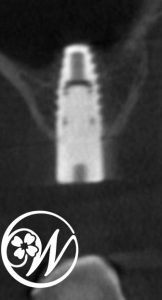

精密検査(レントゲン・CT)を行った結果、右上5番は残根状態で保存が困難、さらに右上6番はすでに欠損している状態であることが分かりました。

術前にはCTデータを用いたシミュレーションを行い、サージカルガイドを使用して埋入位置・角度・深さを正確に設計。

その結果、手術は局所麻酔下で約30分と短時間で、低侵襲に行うことができました。